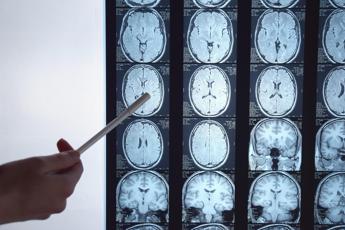

(Adnkronos) – La zona del cervello in cui il cancro si sviluppa può fare la differenza per i malati di glioblastoma, il tumore cerebrale maligno più comune. Se cresce in aree ad alta densità di fibre, la sopravvivenza del paziente dal momento della diagnosi è più breve; viceversa, quando il glioblastoma si localizza in regioni cerebrali a bassa densità di fibre, la prognosi è migliore. La maggiore o minore presenza di fibre risulta quindi “un nuovo indice diagnostico non invasivo che predice la sopravvivenza nei tumori cerebrali”. La scoperta – oggetto di un brevetto italiano e internazionale – è descritta in uno studio pubblicato su ‘Jama Neurology’, frutto di una collaborazione tra le università di Padova, Berlino e Bordeaux e l’Istituto oncologico veneto (Iov) di Padova. Il coordinatore è Maurizio Corbetta, professore di Neurologia, direttore della Clinica neurologica dell’Azienda ospedale università di Padova e Principal Investigator del Vimm, Istituto veneto di medicina molecolare.

La strategia messa a punto da Corbetta, da Alessandro Salvalaggio, ricercatore del Dipartimento di Neuroscienze dell’università di Padova, e da Lorenzo Pini, assegnista del Padova Neuroscience Center e del Vimm, permette dunque di calcolare “un indice di densità delle fibre di sostanza bianca dove cresce il tumore senza necessità di esami specifici, ma soltanto partendo dalla risonanza magnetica cerebrale che tutti i pazienti eseguono prima dell’intervento chirurgico”.